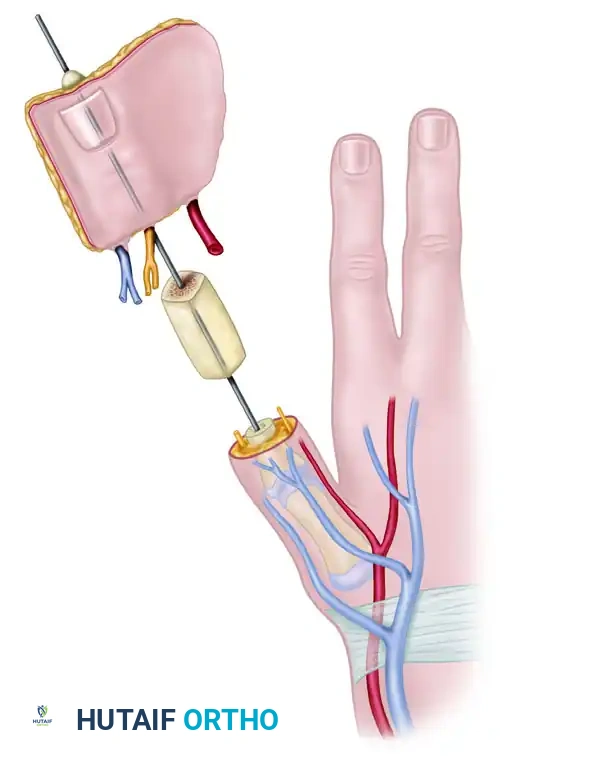

FLAP TRANSFER AND MICROVASCULAR ANASTOMOSIS

With the bone graft rigidly fixed, the harvested wraparound flap is brought to the recipient site.

- Wrapping the Flap: Wrap the soft tissue flap around the iliac bone graft. Ensure the lateral side of the flap is applied to the ulnar side of the bone graft. Trim the bone graft slightly if the soft tissue envelope is too tight; tension on the skin closure will compromise microvascular perfusion.

- Positioning: Loosely suture the flap in place, ensuring the nail is oriented dorsally and the neurovascular pedicle sits comfortably in the first web space without kinking or tension.

- Neural Coaptation: Using an operating microscope, suture the ulnar digital nerve of the thumb to the lateral plantar digital nerve of the flap using 9-0 or 10-0 nylon epineurial sutures. Suture the deep peroneal nerve of the flap to the superficial radial nerve branch on the dorsum.

- Arterial Anastomosis: Perform an end-to-end anastomosis between the princeps pollicis artery and the first dorsal metatarsal artery of the flap. If the princeps pollicis is inadequate, the radial artery at the wrist may be used via an end-to-side anastomosis.

- Venous Anastomosis: Establish arterial flow first to identify the most robust venous outflow. Suture the dorsal digital veins/saphenous tributaries of the flap to the cephalic venous system of the hand.

- Closure: Place small silicone drains beneath the flap if necessary, strictly avoiding proximity to the microvascular anastomoses. Close the skin loosely.